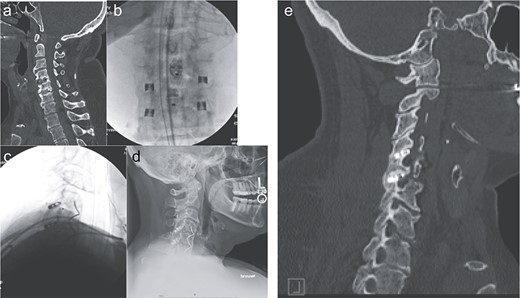

The patient is placed in prone position with the face rested on a regular foam pad and a shoulder pusher in place to visualize the lower cervical segments. Two C-arms are placed in the antero-posterior (AP) and lateral positions, respectively. The posterior cervical midline skin incision is ~0.5–1 inch long and typically located around the C7 or T1 spinous process. A 10-blade is used to make two incisions in the posterior cervical fascia, slightly cranial to the skin incision, one on each side of the spinous process. Up to three levels can be treated through the same skin incision, due to the lordotic alignment of the cervical spine. The procedure is continued using the dedicated instruments, which are used a specific sequence: the access chisel, the decortication trephine, the guide tube, the decortication rasp, the fork mallet, the decortication burr, the cage inserter, and the bone graft tamp. The access chisel is used to bluntly penetrate the paraspinous muscles, targeting the facet joint of interest on both the AP and lateral fluoroscopic images. Once the tip of the access chisel reaches the posterior aspect of the facet joint, gentle tapping allows it to penetrate the posterior facet capsule and enter the joint; this is confirmed both by lateral fluoroscopy and a tactile feel. Once in the facet joint, an AP fluoroscopic image is obtained to confirm that the access chisel is in the middle of the joint, and then the chisel is advanced until its tip encounters the cranial pedicle. The decortication trephine is then inserted over the access chisel and used to decorticate the posterior aspects of the superior and inferior facets. The guide tube is inserted over the access chisel, which is then easily withdrawn. The decortication rasp and burr are then used for preparation of the interfacet space. Finally, the cage is packed with graft material of choice and inserted into the joint using the cage inserter until the tip of the cage touches the cranial pedicle. Optionally, a bone screw can be inserted through the cage and into the superior facet, to maximize stability. The cage inserter is then detached from the cage and removed. Final images of the construct are obtained (Fig. 2).

Imaging showing the minimally invasive interfacet cages technique. (a) Computer tomography imaging, sagittal view, showing lack of interbody fusion after ACDF 4-5-6. (b) AP intraoperative fluoroscopic images showing the placement of the interfacet cages. (c) Lateral intraoperative fluoroscopic images showing the placement of the interfacet cages. (d) Lateral X-ray showing a solid fusion at 1 year postoperatively. (e) Computer tomography imaging, sagittal view, showing a solid fusion at 1 year postoperatively.